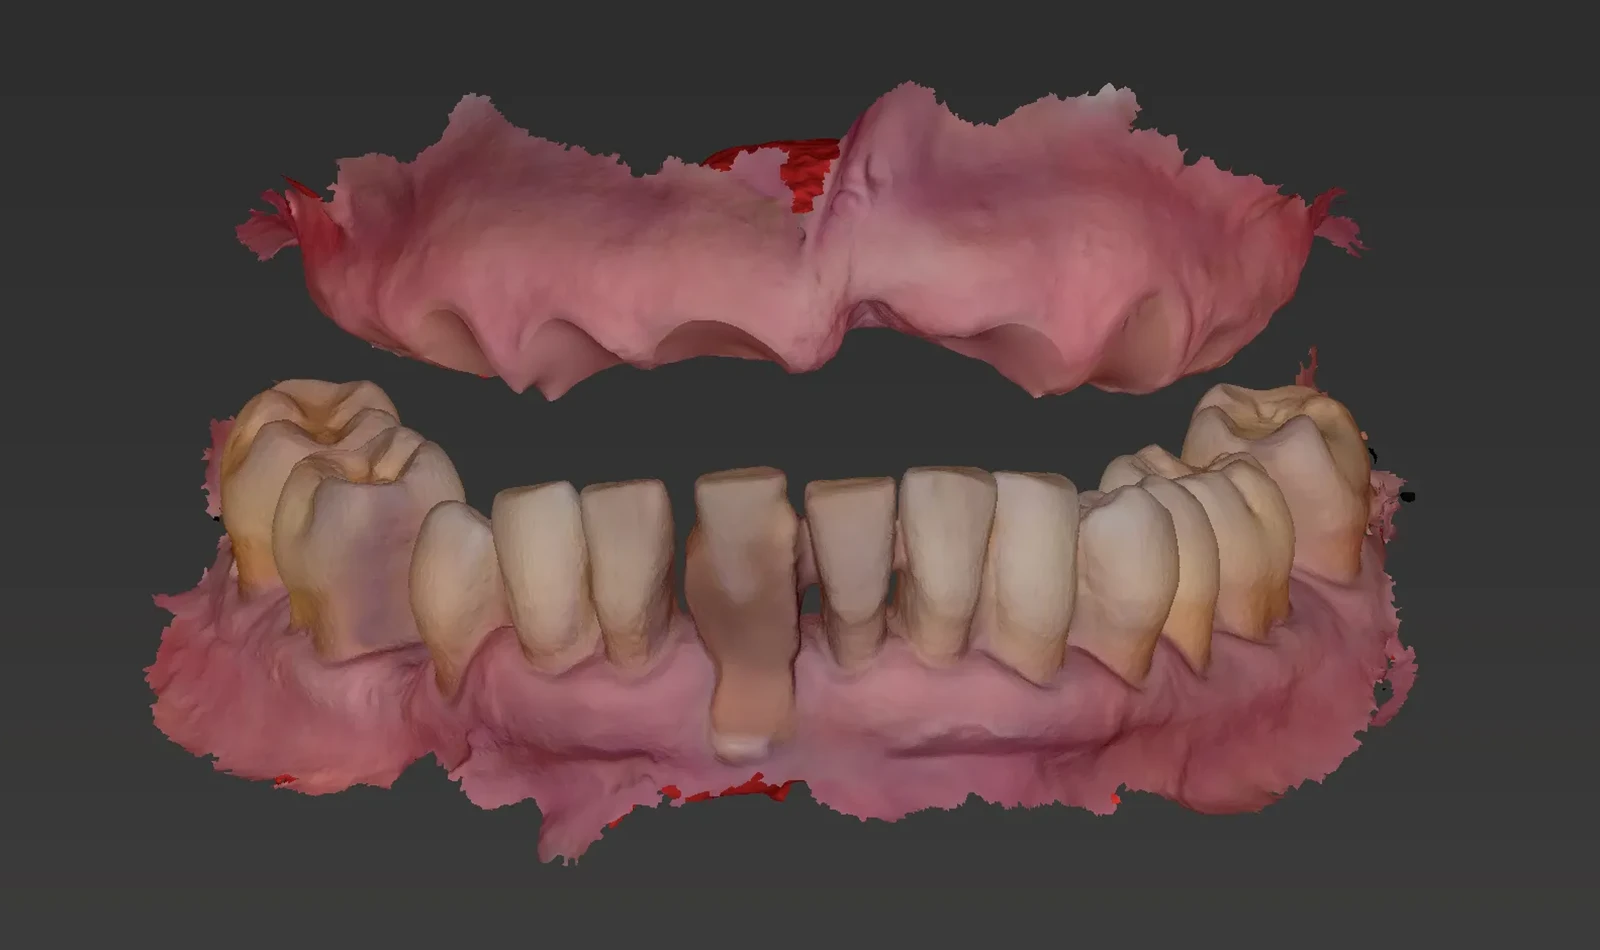

Paciente de 60 años, sufría porque sus dientes se movían y temía perderlos todos, pero gracias a la cirugía guiada y la técnica de carga inmediata, en un solo día Merche recuperó una sonrisa fija y natural. Volvió a comer, hablar y sonreír con mayor comodidad desde el primer momento.